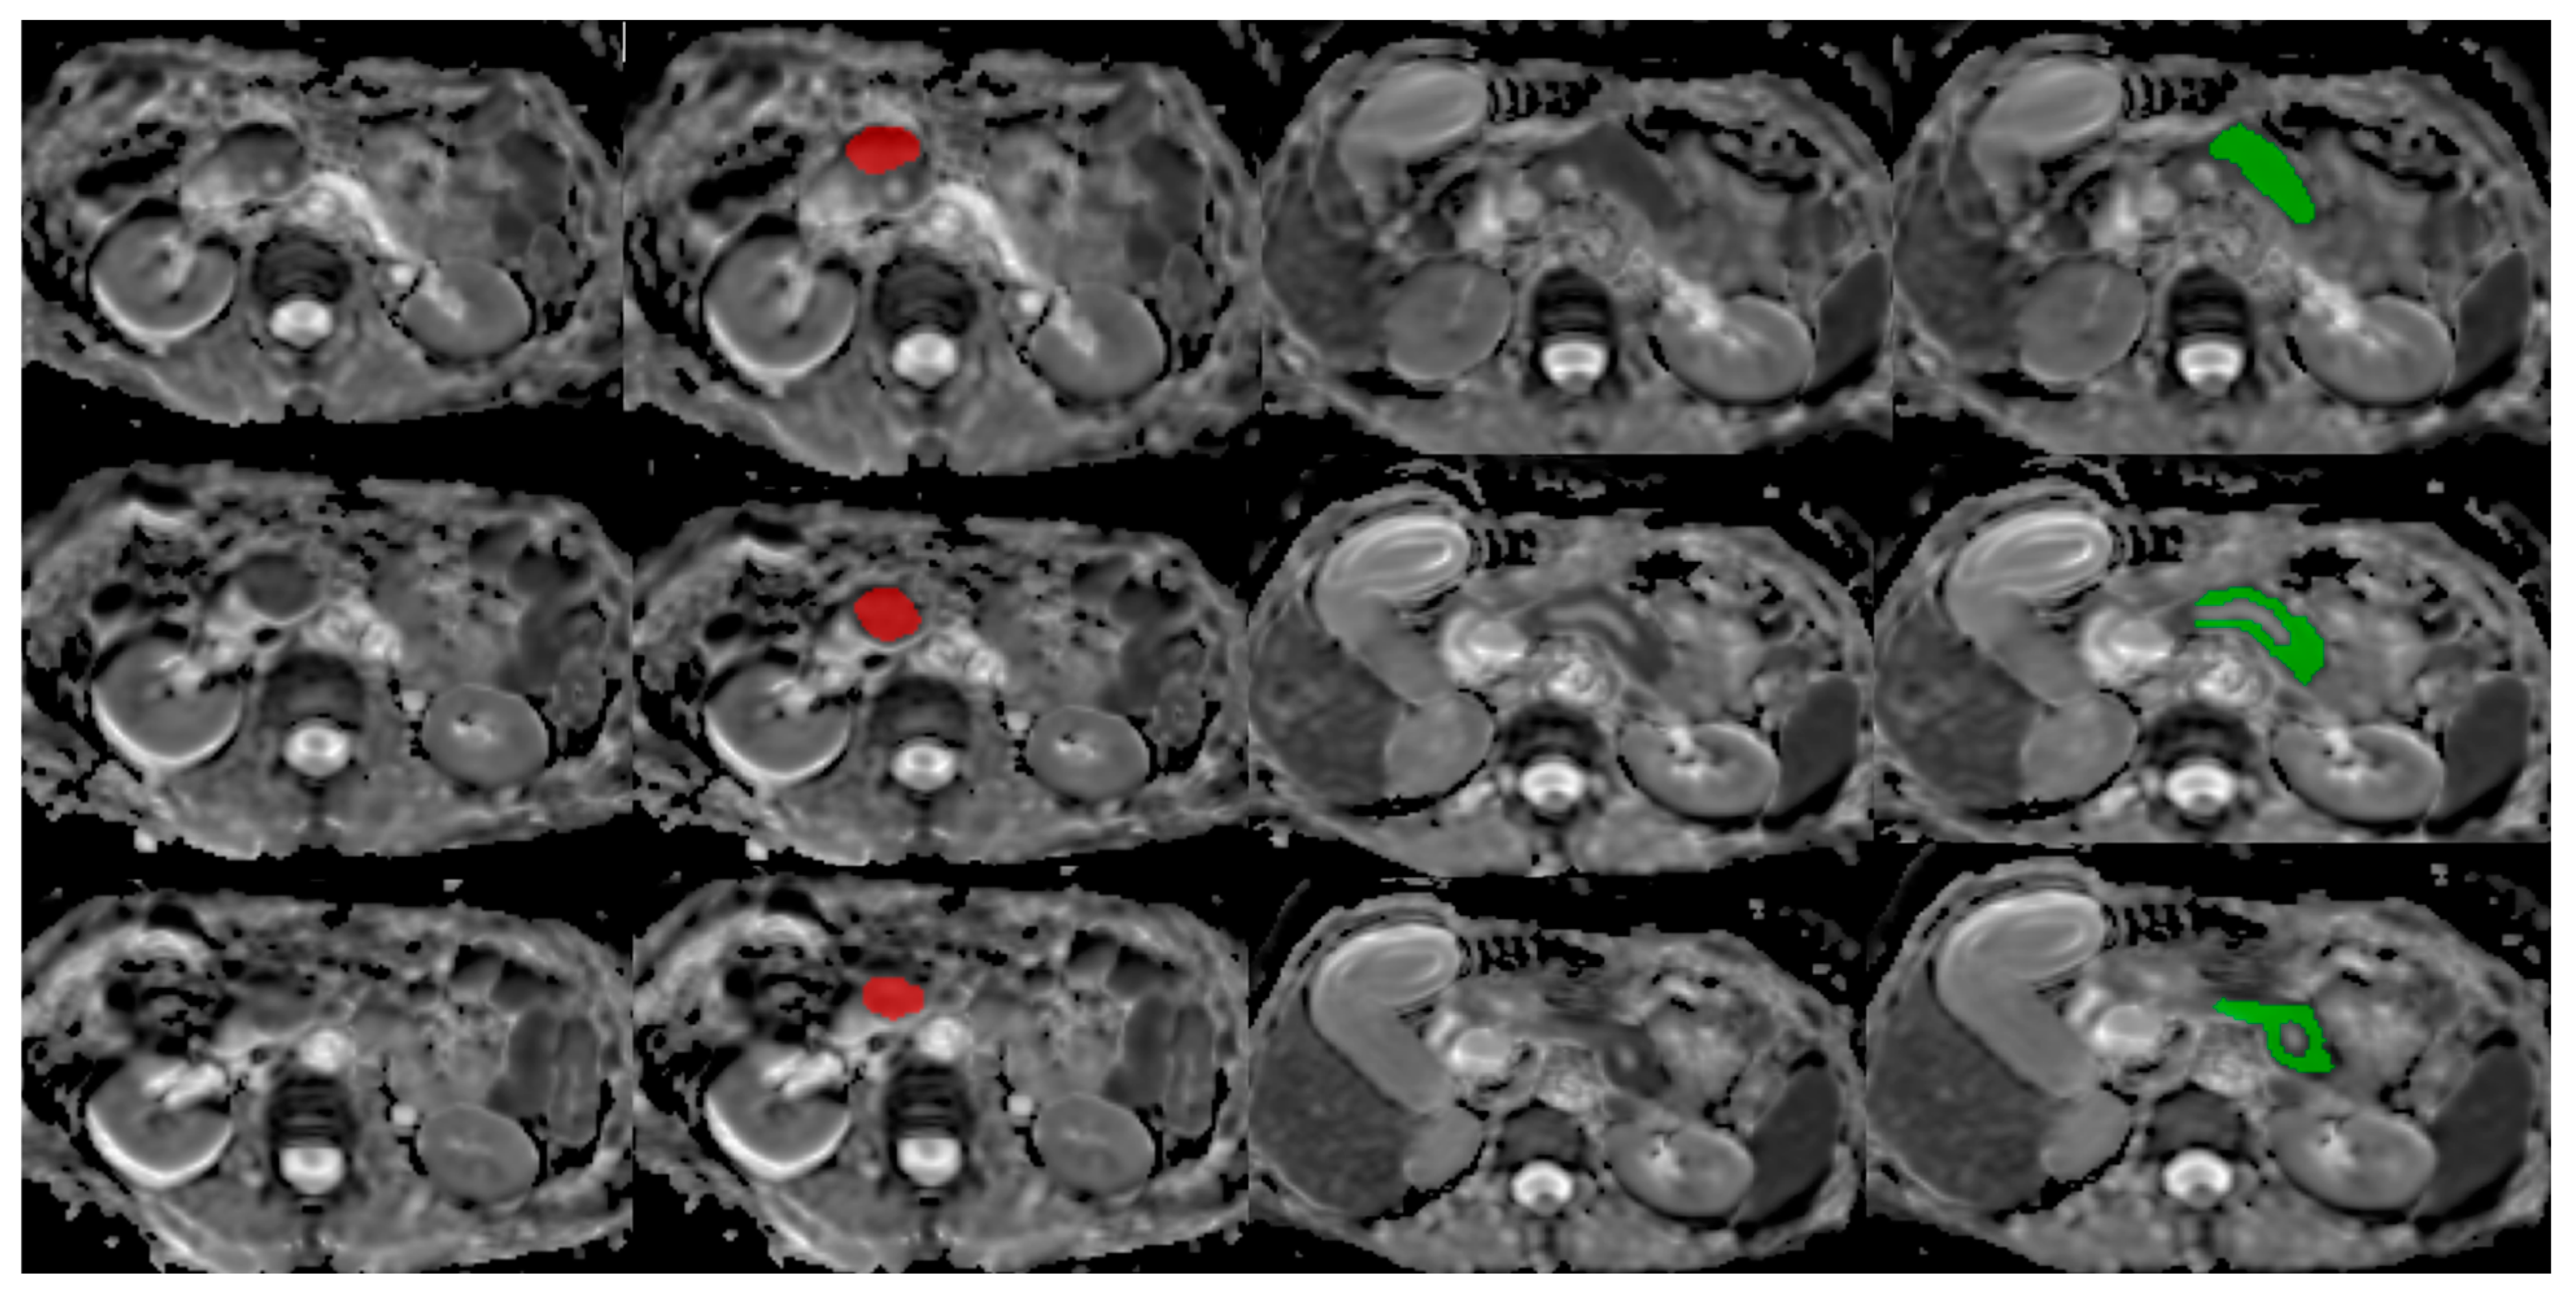

2.3. MRI Analysis

2.3.1. Database